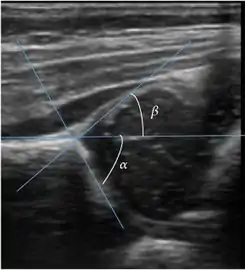

Ultrasound is the first-choice technique for diagnosis of newborns hip dysplasia. In experienced hands with appropriate technology, ultrasound can also be useful during the first year of life. Some European healthcare systems encourage universal ultrasound screening in neonates between the sixth and eighth weeks. Although it shows higher initial costs caused, it leads to significant reduction in the total number and overall costs of dysplastic hips undergoing operative and nonoperative treatment.[1]

Ultrasound allows categorizing pediatric hips, according to Graf’s criteria, in four main types: normal, immature, and dysplastic (subluxed and dislocated). This classification is based on measurements of the acetabular inclination angle (alpha), cartilage roof angle (beta), and infant age. The femoral head coverage can also be determined by dividing the length of the femoral head covered by the acetabular fossa and the diameter of the femoral head. Its lower normal limits are 47% for boys and 44% for girls (Figure 11).[1]

Figure 11:

Useful ultrasound measures in neonatal hip sonography, alpha and beta angles.[1]

Measurement of femoral head coverage.[1]